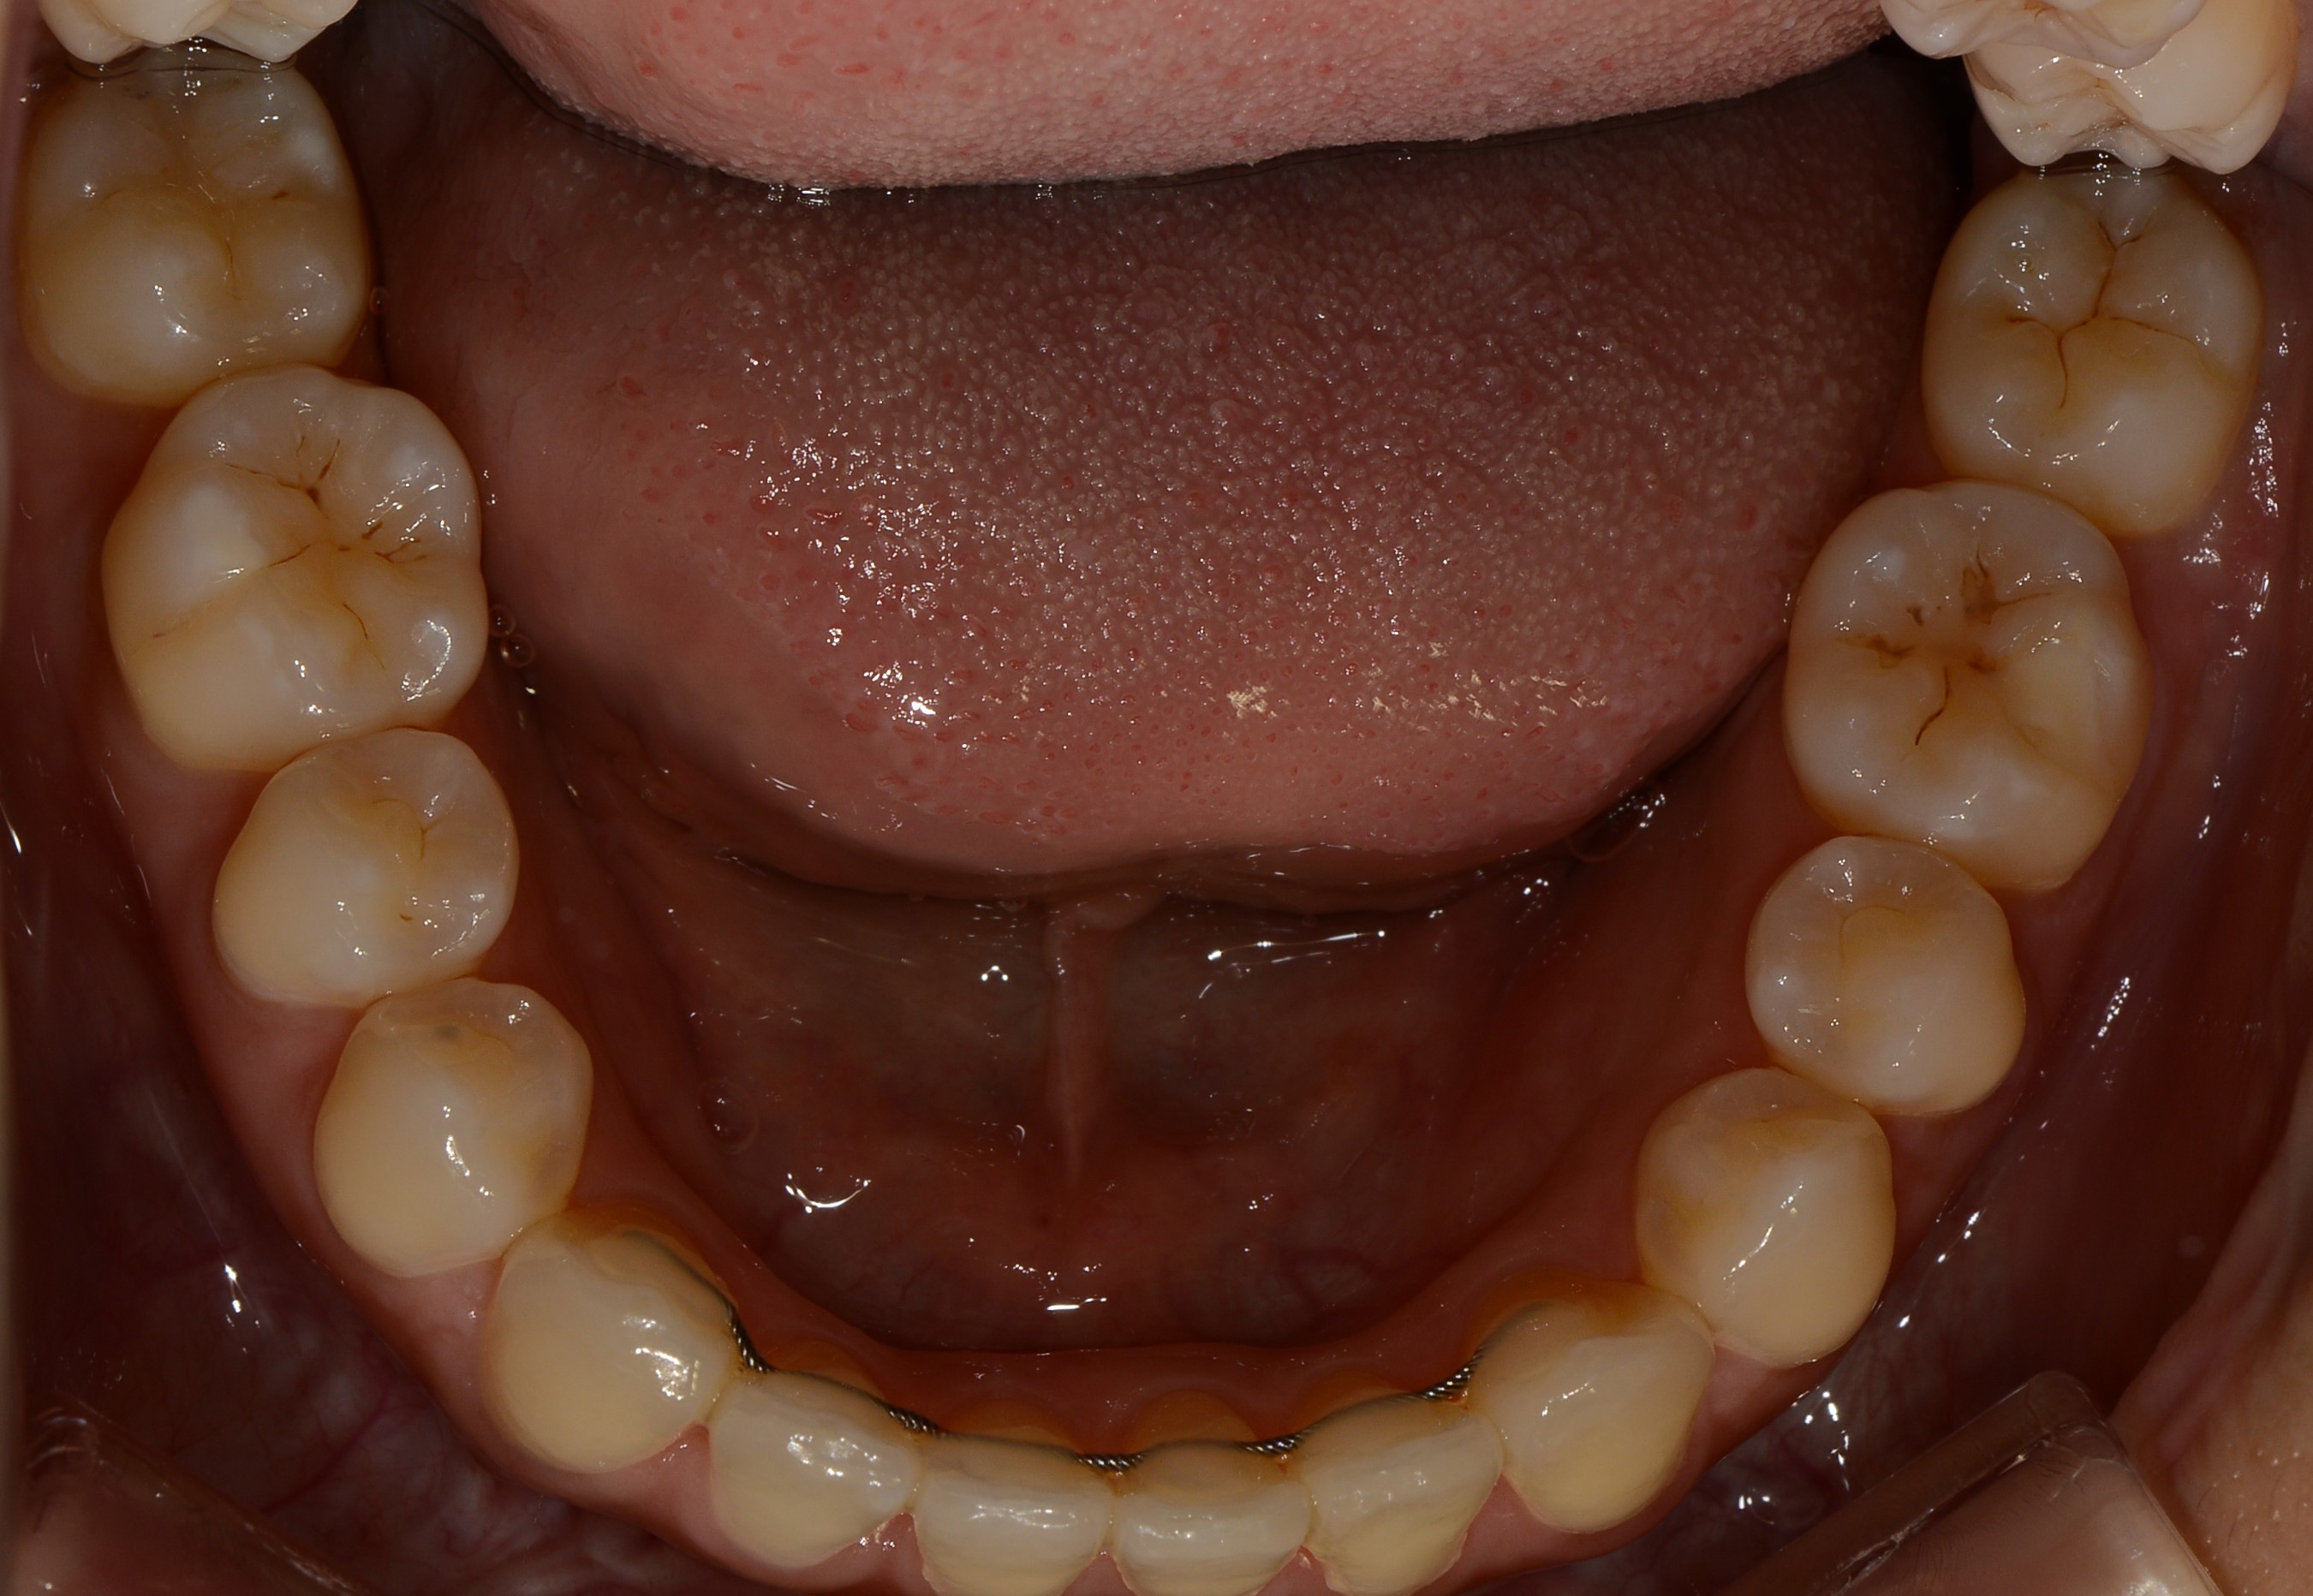

치료 후 사진입니다.